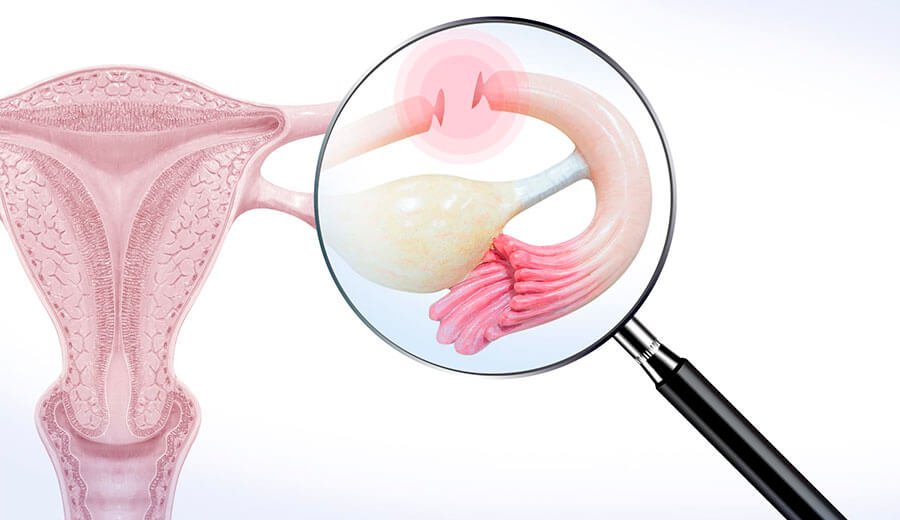

Laqueadura tubaria

Procedimento cirúrgico no qual as trompas de falópio são bloqueadas para prevenir a gravidez. É uma opção segura e eficaz para mulheres que não desejam ter filhos no futuro.

A reversão de laqueadura, também conhecida como recanalização tubária, consiste em desfazer a obstrução ou reconectar as trompas, permitindo o fluxo de óvulos dos ovários para o útero, possibilitando a concepção natural.